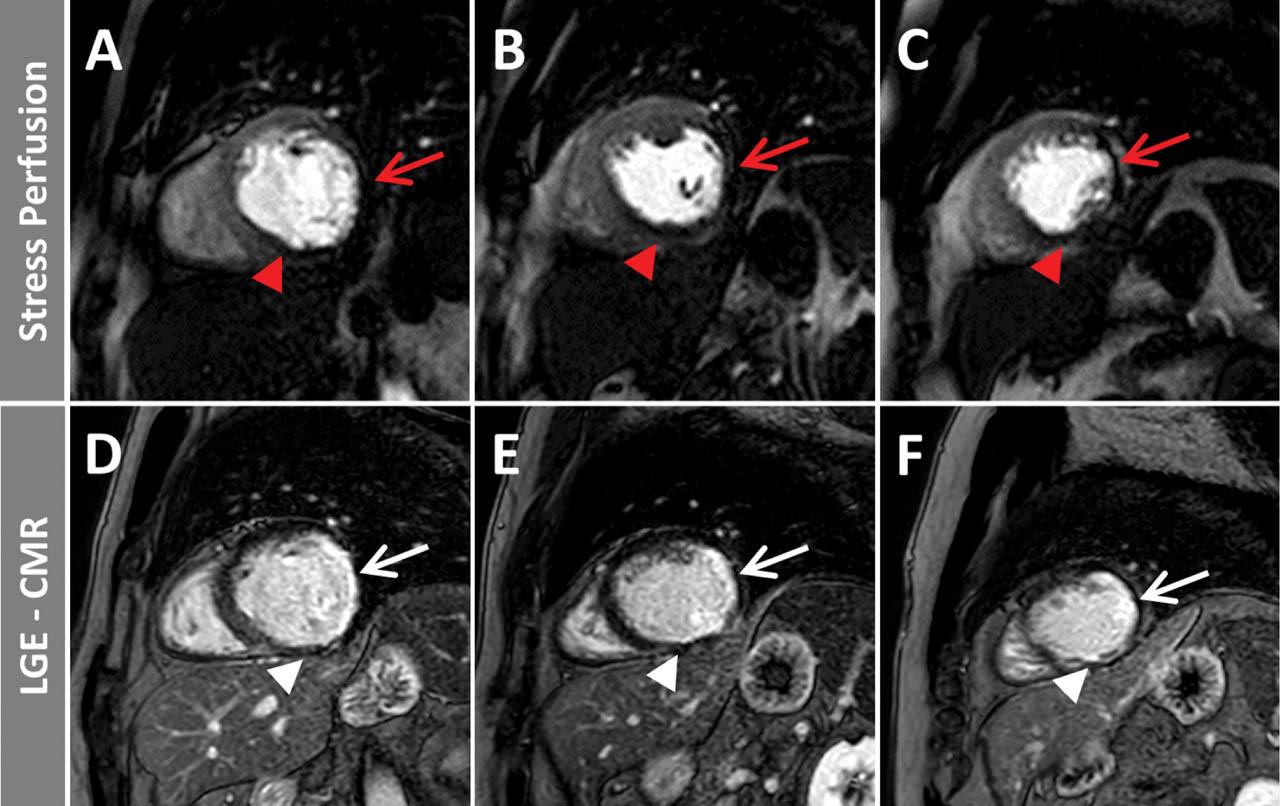

Figure 2

Stress perfusion during adenosine-hyperemia (A, B, C) and LGE images (D, E, F) in basal (A, D), mid-ventricular (B, E) and apical (C, F) short-axis. In the lateral wall segments, an inducible perfusion deficit can be visualized (red arrows) in the absence of scar (LGE), suggesting a hemodynamically relevant stenosis in the territory of the circumflex coronary artery.